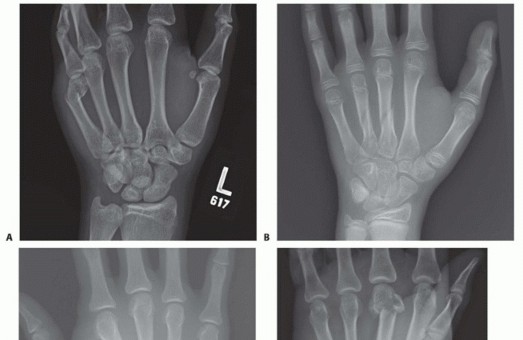

TECH FIG 4 • A-C. Patient with torsional injury to long and ring fingers leading to spiral fractures of the third and fourth metacarpals. The combined injury made it possible for malrotation to develop. D.

TECH FIG 4 • (continued) G,H. Motion at 6 weeks after surgery. The periosteum is elevated at the fracture site to assist with assessment of fracture reduction. As much of the interosseous muscle is left attached to the metacarpal as feasible to preserve blood supply to the bone.The fracture is reduced and provisionally stabilized with reduction clamps (TECH FIG 4D).

LAG SCREW FIXATION

Long oblique and spiral fractures whose lengths are at least twice the diameter of the bone at the level of the fracture are amenable to limited fixation with screws only (see TECH FIG 4A-C).Appropriately sized lag screws (1.4 to 2.7 mm) are placed. Typically, two or three screws are used (TECH FIG 4E,F).The first screw is placed perpendicular to the fracture in order to compress it and the second screw is placed perpendicular to the bone to resist longitudinal forces.In order to get proper compression with a lag screw construct, it is important to overdrill the near cortex.When using a 2.0-mm screw system, a 1.5-mm drill bit is used to drill both cortices. The near cortex is then overdrilled with a 2-mm drill bit.A countersink is used to maximize contact between the head of the screw and the bone. The size of the screw is measured and an appropriately sized screw is placed.The periosteum and interosseous muscle fascia are reapproximated to cover the screws. The juncturae tendinum are repaired and the skin is closed in standard fashion.The hand is then immobilized with the MP joints flexed 70 to 90 degrees with a forearm-based splint. Early motion can be started as early as 4 to 7 days, depending on fracture stability (TECH FIG 4G,H).